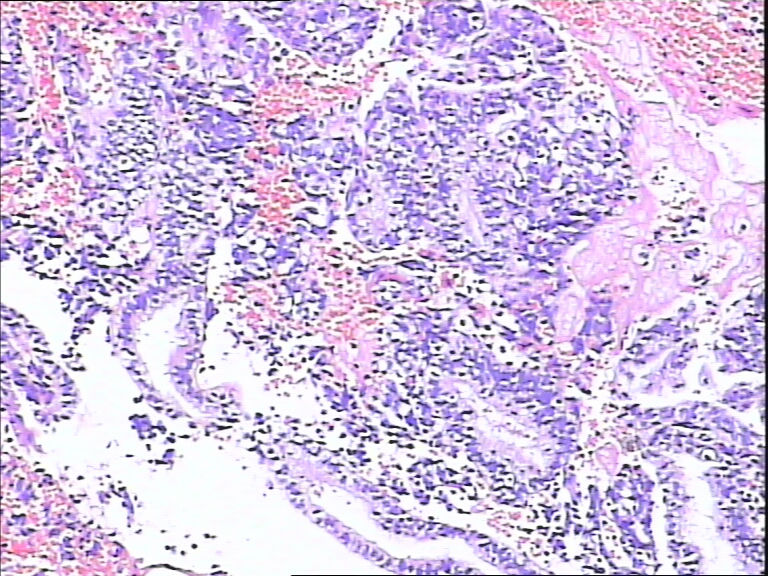

41岁,停经5年再出血。

• 宫内膜图2

图2

流血期子宫内膜,腺体反应不同步

腺体反应不同步,部分增生期改变,部分上皮细胞有核下空泡呈早分泌期改变,是用过药物?

片子不是很清楚,像是月经期子宫内膜

流血期子宫内膜,腺体反应不同步。

腺体增生,部分腺上皮有分泌。